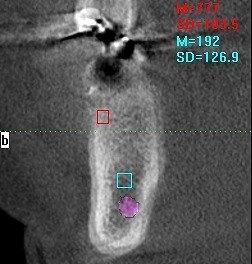

術前のCTになります

インプラント埋入時になります

5mmの11,5mmというインプラントを埋入しています